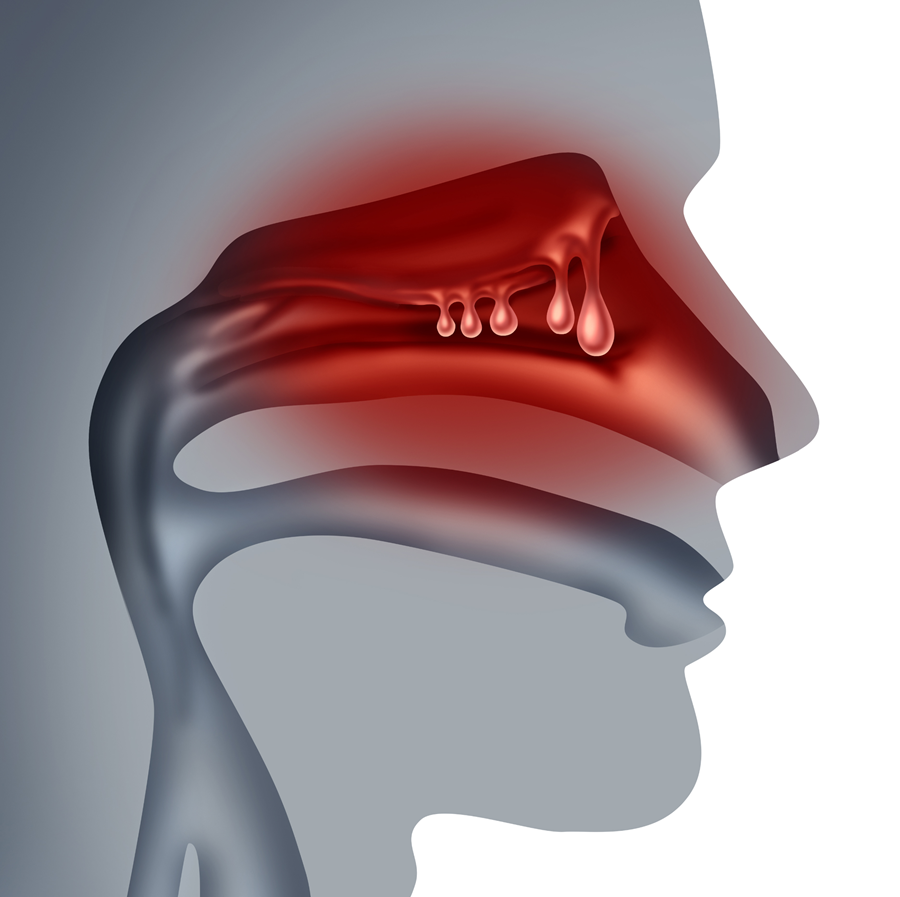

Biologische therapieën en ernstige chronische rhinosinusitis met neuspoliepen: een Belgische real-worldstudie

Van de 167 patiënten met CRSwNP kregen 144 mepolizumab en 23 omalizumab. Na 24 weken verbeterden de gerapporteerde uitkomsten en de NPS duidelijk bij beide behandelingen, met significante effecten vanaf 12 weken en een verdere daling van de NPS onder